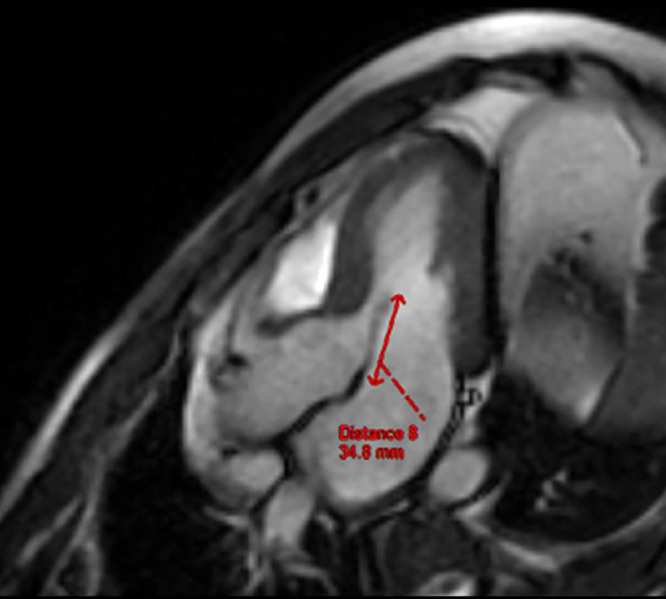

An Unusual Etiology of Presyncopal Episodes: Dynamic Left Ventricular Outflow Tract Obstruction Secondary to an Elongated Anterior Mitral Valve Leaflet.